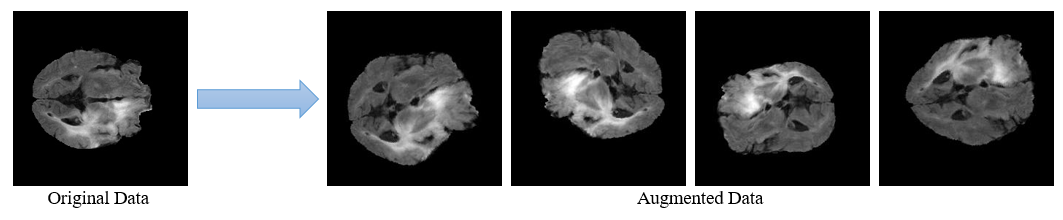

pytorch/dataset.pypreprocess.py: Code for data pre-processing. Using this, original image(240×240×155×4) can be diveded into 155 image pieces(240×240) of the specific mode. Also, original label(240×240×155) can be divided into 155 label pieces.